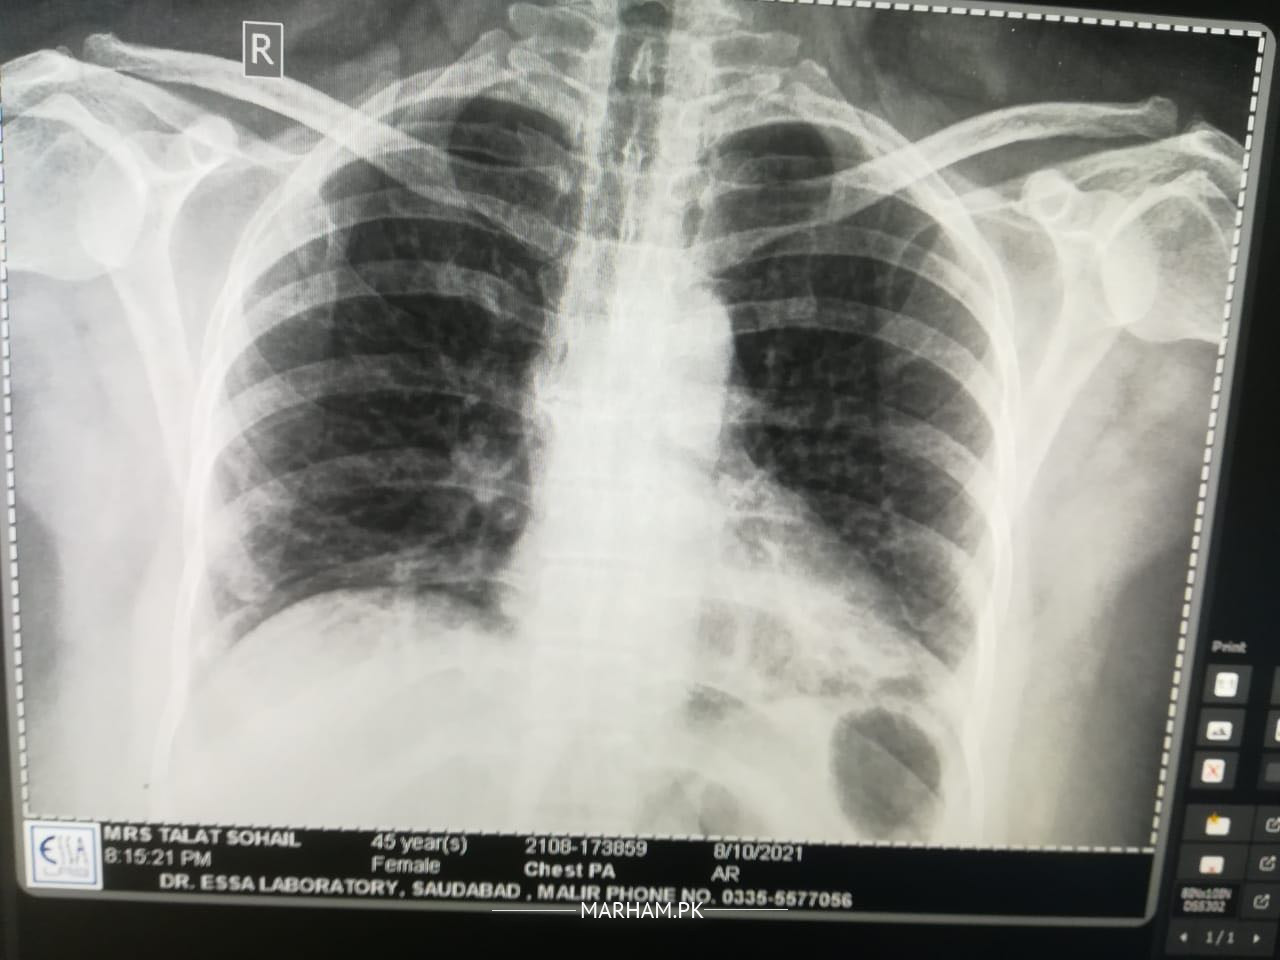

Please examine the x ray and guide is this ok xray is attached. NOTE: She had viral few days back resulting in serious cough and diagnosed with chest infection…. This xray is taken after recovery

comparison with previous x-ray required

yes chest infection

Previous xray